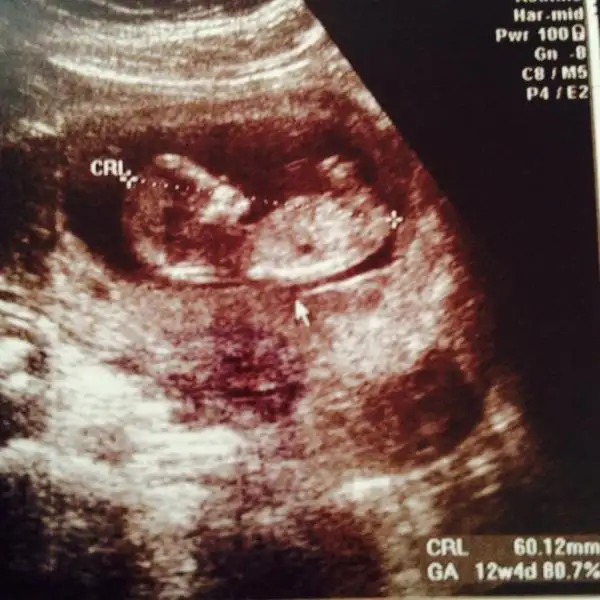

Aslında daha önce sormuştum ama tek bir arkadaş yorum yazdı belki farklı görüşler olur diye tekrar fikir almak istedim :) burda 12+1 iz normalde ama 3 gün önden gidiyoruz 12+4 görünüyor o yüzden minnağım :)

Eki Görüntüle 1214628 %90 kız dedi bir hekim diğer başka hekim birşey söyleyemedi

eger o çıkıntı ayak değilse erkek gibi duruyorKIZLAR SİZCE BENİMKİ NE

Kiz canım öyle gozukuyorKIZLAR SİZCE BENİMKİ NE